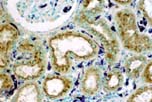

The Pathology Research Services Laboratory at UW Medicine Department of Pathology provides expertise in a broad spectrum of morphologic studies required for interpretation of disease processes.

The primary morphologic techniques offered by the Pathology Research Services Laboratory, on a fee for service basis, include paraffin and frozen tissue processing and embedding, routine histology including special histologic stains, tissue enzyme histochemistry, immunohistochemistry (IHC), in situ hybridization (ISH), immunofluorescence (IF), TUNEL staining, and ancillary techniques (such as competitive inhibition assays and Western blotting necessary to ensure the specificity and sensitivity of reagents).